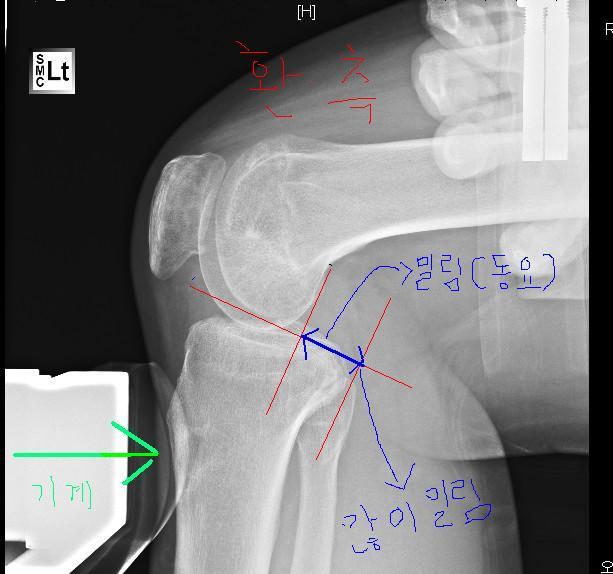

그림 편집능력이 비루하지만 이해해주세요 ^^ 위사진은 제 다리사진입니다. 퍼온게 아니고요..^^

위쪽인 환측(수술한다리) 아래가 건측(안아픈다리)입니다.

자 스트레스뷰<엑스레이>사진을 찍으면 위와 같이 아픈다리 다친다리를 찍습니다. 경골부분을 도구로 밀면서 찍는데요

각 엑스레이사진에서  선을 그어서 파란색선 즉 밀리는 부부을 측정하고  mm수를 의사들이 잽니다.

자 저같은 경우를 살펴봐도 위 사진이 훨씬 더 많이 밀리는게 보이시죠? 이렇게 건측과 환측을 측정해서 동요MM수를 의사들이 보는것입니다.